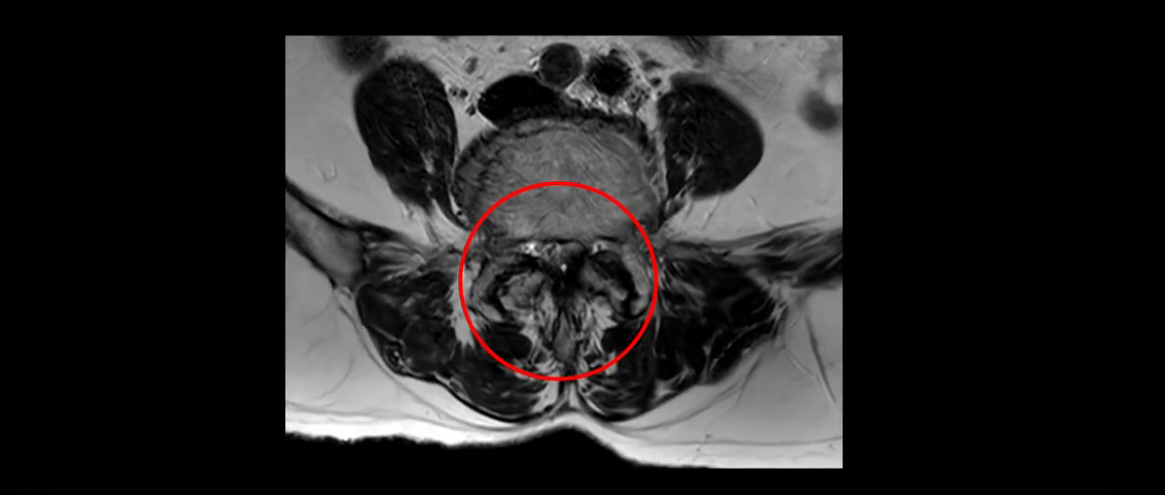

먼저 이분 MRI를 보고 자세히 설명해 드린 후 어떻게 허리 여러 마디에서 협착과 전방전위로 신경이 심하게 눌려 보이는 환자가 수술 없이 좋아질 수 있는지, 또 치료는 어떻게 하는지 설명해 드리겠습니다.

이분 MRI 보시면 허리 3마디의 퇴행이 매우 심합니다.

또 척추관협착도 매우 심합니다.

척추관이 심하게 좁아져 있습니다.

이렇게 신경 구멍들이 좁아져 있고 신경이 눌리니까 엉덩이와 다리가 너무 저리고 아파서 아예 일어서질 못하니까 휠체어를 타고 병원에 내원하셨는데요. 그럼 어떻게 이분처럼 신경이 눌려있는 환자분들을 수술 없이 치료해서 잘 걷게 만들고 엉덩이와 다리가 저리고 아픈 증상이 사라지게 할까요? 지금부터 설명해 드립니다.